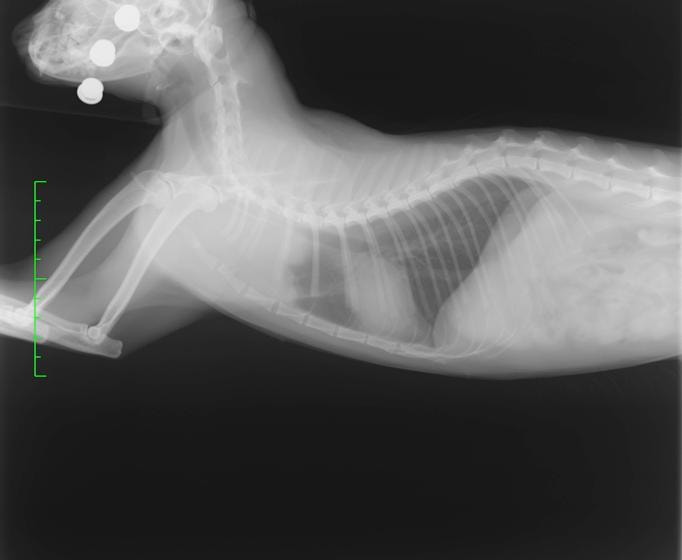

診断:胸部レントゲン検査にて、前縦隔領域に不透過性亢進領域を確認しエコー検査にてFNAを実施。細胞診の結果「低〜中分化型リンパ腫」と診断

前胸部にみられた不透過性領域の退縮が認められます